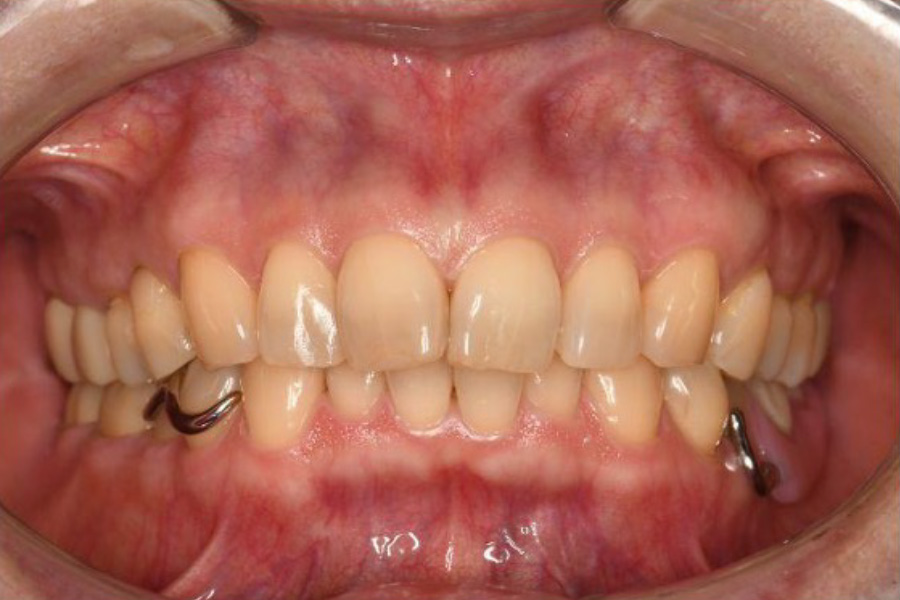

治療後

(義歯未装着)

(義歯装着時)

【口腔内写真】

義歯装着前の口腔内状態(左下)

義歯を外した状態の画像を見ると、治療の初期段階で行った「地盤管理」がいかに成功したかが一目でわかります。

通常、抜歯後の「地盤(歯ぐきや骨)」は時間とともに痩せ、大きく窪んでしまいます。しかし、本症例では戦略的抜歯と同時にリッジプリザベーション(歯槽骨保存術)を施したことで、欠損部の歯槽堤(歯ぐきの盛り上がり)が見事に保存されています。

その高さは、隣接する健康な歯(4番・5番)の歯頸ライン(歯ぐきとの境目)とほぼ同じレベルに維持されています。この平坦で強固な「プラットフォーム」が完成しているからこそ、その上に載る精密な金属床義歯は、ガタつくことなく強力な「噛む力」をしっかりと受け止めることができるのです。

【口腔内写真】義歯装着時の左側観

- 精密金属床義歯とRPIクラスプ:

『力を逃がす』高度なエンジニアリング

左下奥歯の欠損部には、最新の設計に基づいた精密金属床義歯が装着されています。注目すべきは、第二小臼歯にかかっているRPIクラスプの「Iバー」です。

これは、噛む力が加わった際に、支えとなる歯を「ねじる」ような有害な回転力を逃がす特殊な構造です。建築で言えば、地震の揺れを吸収する「免震構造」のような役割を果たし、残された貴重な歯(地盤)の寿命を最大限に延ばします。 - ジルコニアクラウンへの更新: